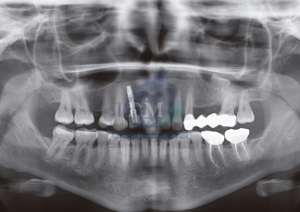

Paciente masculino de 33 años acude para una revisión general. A la evaluación de la radiografía panorámica se observa la neumatización de ambos senos maxilares, múltiples